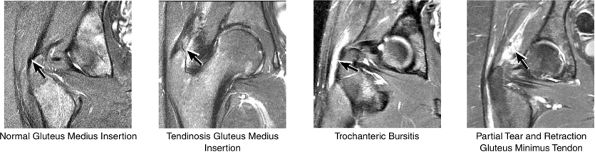

|

FIGURE 3.35 / Greater Trochanter.

or secondary to communication with the hip joint. Trochanteric bursitis suspected on coronal images is confirmed on axial images.